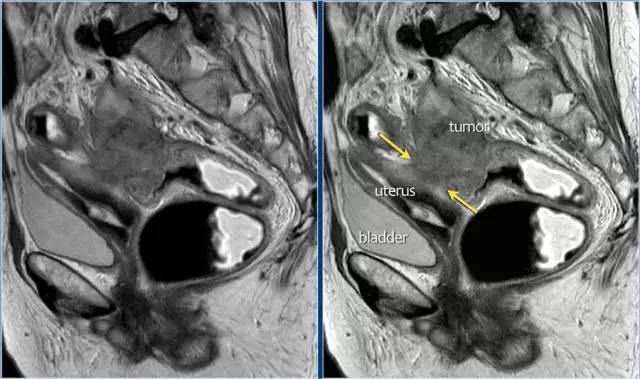

图 16 在矢状 T2W 图像上,直肠和阴道后壁之间有脂肪平面的损失。在轴向图像上,看到肿瘤的相对低的信号强度延伸到阴道的后壁(箭头)

以下 5 幅图例请连续观看:

图 17~21 肿瘤的低信号强度延伸到阴道的后壁(箭头)

图 22 浸润到子宫后壁的肿瘤